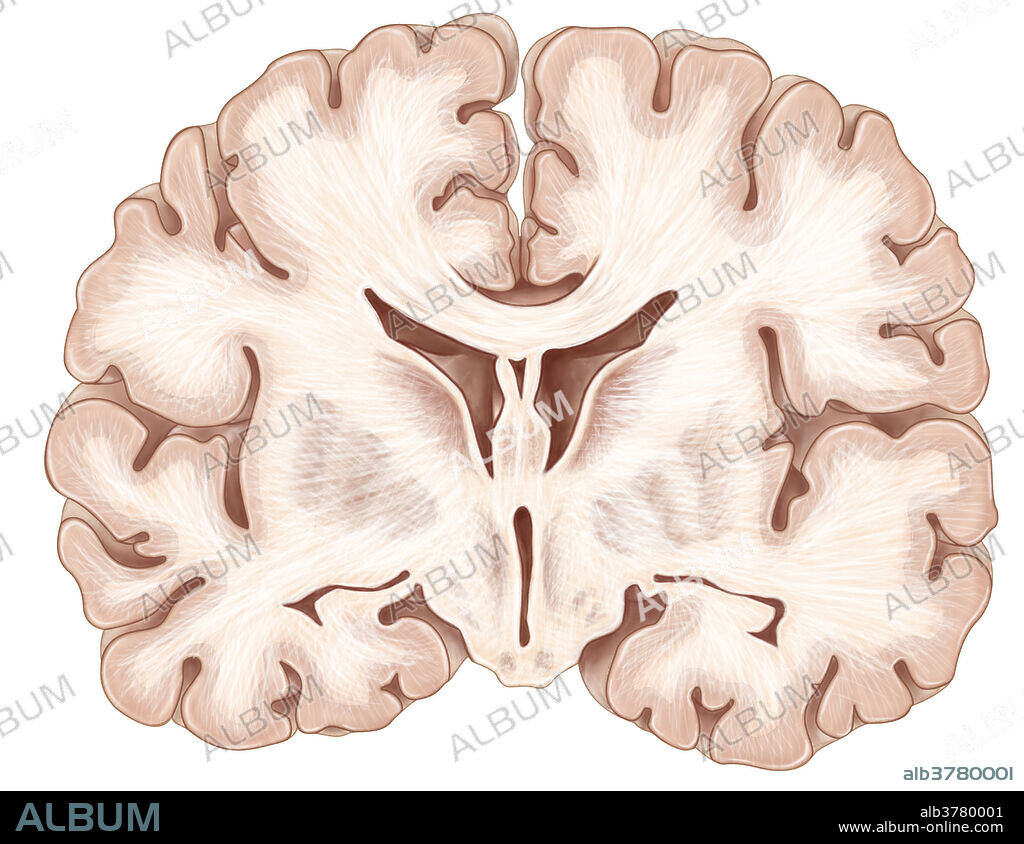

Brain, Coronal Section

Brain, Coronal Section

An illustration of a coronal (frontal) section of the brain.

ANATOMIA • ARTE • BASALES • BLANCO • CALLOSO • CAUDADO • CEFALORRAQUÍDEO • CEREBRAL • CEREBRO • CNS • CUERPO • FONDO DE SACO • FONDO • FRONTAL • GANGLIOS • GRIS • ILUSTRACION • LATÉRAL • LOBULO • MEDICINAL • NERVIOSO • NIGRA • NORMALES • NUCLEO • OBRA DE ARTE • PALIDO • PUTAMEN • SECCIÓN • SECTION • SISTEMA • TÁLAMO • TEMPESTAD • TEMPORAL • TEMPORALES • TIEMPO: TEMPESTAD • TIEMPO: TORMENTA • TORMENTA • TRAMO • VENTRÍCULO